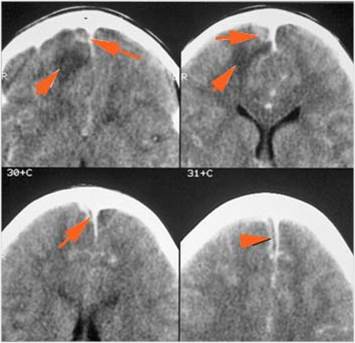

There is brain edema specifically involving the frontal and temporal lobes.

There is cerebritis specifically involving the frontal and temporal lobes.

There is brain abscess specifically involving the frontal and temporal lobes.

There is likely meningitis, meningoencephalitis with complicating hydrocephalus or brain herniation.